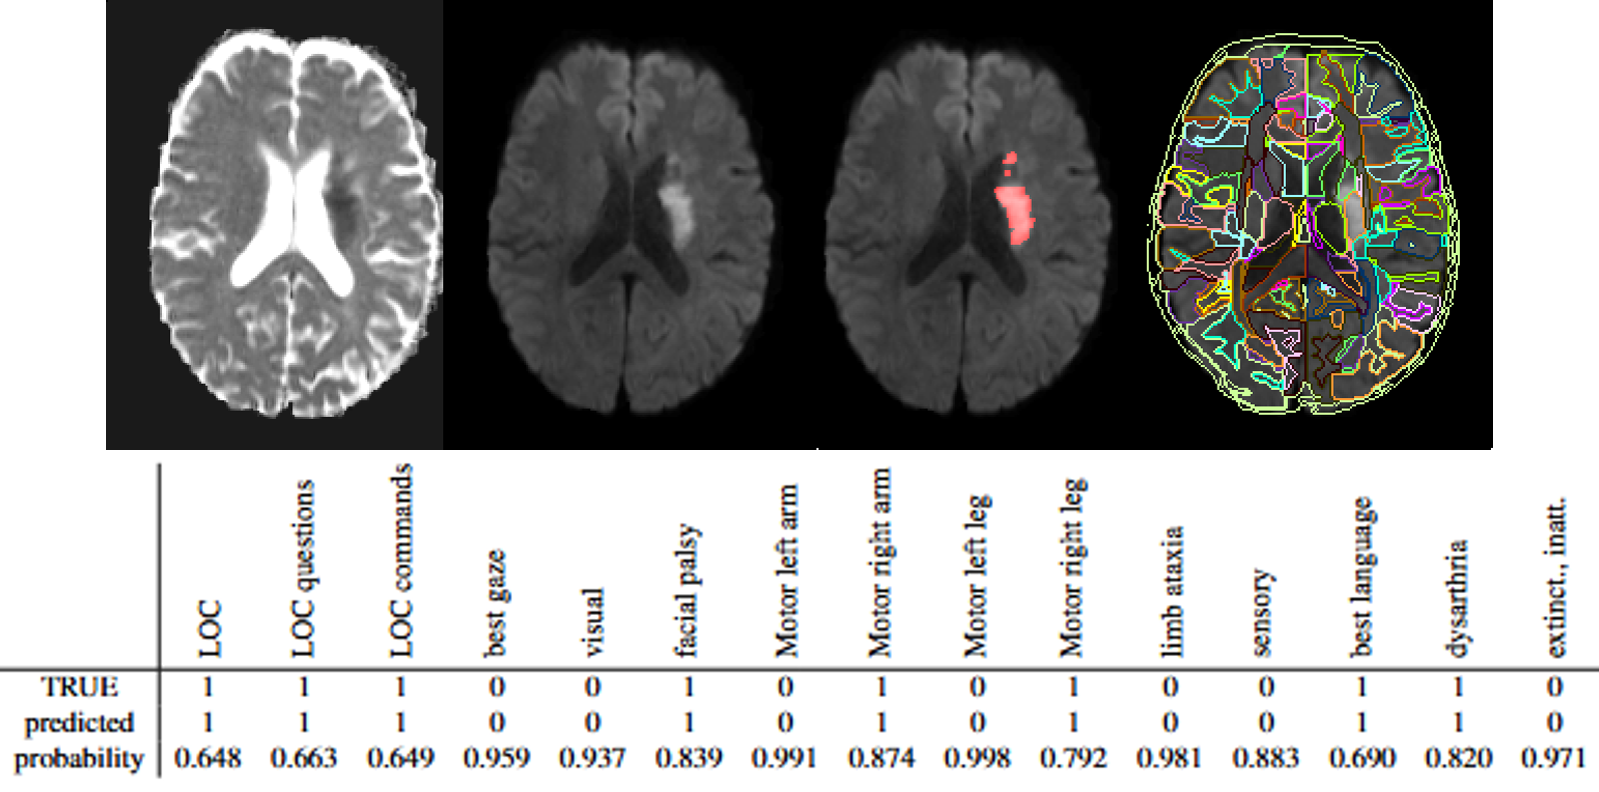

Automated Prediction of Domain-Specific NIHSS from MRI Using Machine Learning for Acute Stroke Assessment

ISMRM 2026